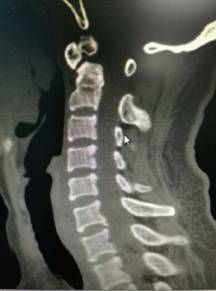

颈椎前路减压融合内固定术治疗脊髓型颈椎病

优点:直接减压,彻底解决突出问题,稳定。

颈椎后开门Arch钛板固定术治疗颈椎后纵韧带骨化症

优点:减压范围广,疗效缺切,保留颈椎的活动度。

2、脊柱手术微创化理念:采用椎间孔镜等脊柱微创手段实施各种脊柱微创手术。治愈了大量的腰间盘突出症、腰椎管狭窄症、颈椎病患者。采用PVP、PKP术治愈了大量高龄脊柱压缩性骨折患者,近年来累计完成4000例该微创手术。60%的脊柱病人可以进行微创手术,具有创伤小、效果好、安全性高、恢复快、术后不需长期卧床等特点。微创手术保持极高的优良率与可靠性。脊柱微创技术居于淮海经济区先进水平。我院在淮海经济区率先开展颈椎微创手术。